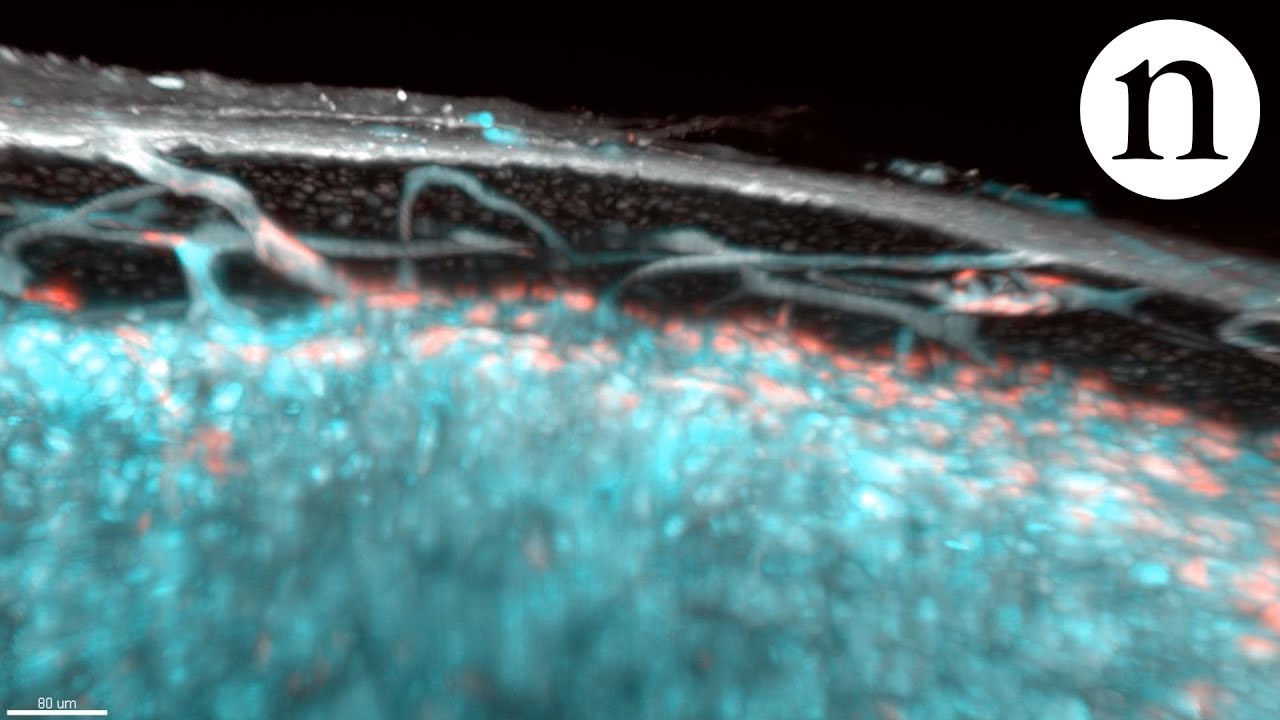

Zu bringen, die feinen Blutgefäße, die Wissenschaftler haben die Knochen von Mäusen eine Substanz namens этилциннамат. Mit Licht-Mikroskopie und Röntgen, sahen Sie Hunderte von winzigen Tunneln. Es stellte sich heraus, dass in der Tibia von Mäusen enthält mehr als 1000 solcher Kapillaren, durchzogen von mehr als 80% des arteriellen Blutes. Dieselben Tunnel, aber breitere, wurden entdeckt und in den Knochen des Menschen-ehrenamtliche — Sie wurde selbst der Autor der Studie, Mathias Гюнсер.

Winzige Kanäle haben den Titel «транскортикальные Gefäße», denn Sie durchdringen auch Feste, kortikale Schicht des Knochens. Die ersten Vermutungen über Ihre Existenz gebracht wurden иммунологом Mathias Гюнсером, наблюдавшим über die Umstellung der gefärbten Blutkörperchen im Körper von Labormäusen. Er bemerkte, dass Sie passieren sogar innerhalb einer festen Schicht und nicht Naidoo über diese Merkmale keine Erwähnung in den Büchern, schuf ein spezielles Forschungsprojekt.